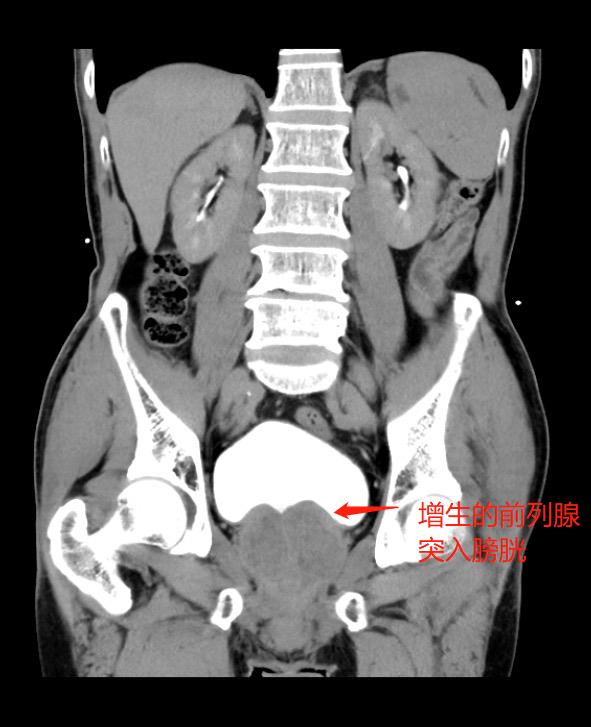

家住长沙78岁的李大爷排尿困难10余年,并且反复急性尿潴留,夜间排尿7、8次,严重影响生活质量。几经辗转,李大爷慕名来到捷克论坛 马王堆院区泌尿四科求诊。经检查发现,李大爷患有前列腺增生。泌尿四科主任杨科团队讨论后,决定为李大爷行经尿道前列腺钬激光剜除术。术后,李大爷排尿十分通畅,解决了困扰他多年的难题。

“前列腺肥大症是一种机体衰老的表现,为老年男性常见疾病。”杨科表示,前列腺增生的发病率随着年龄增大逐渐增加。男性在45岁以后可有不同程度的增生,多在50岁以后出现症状,而60岁以后症状更加明显。